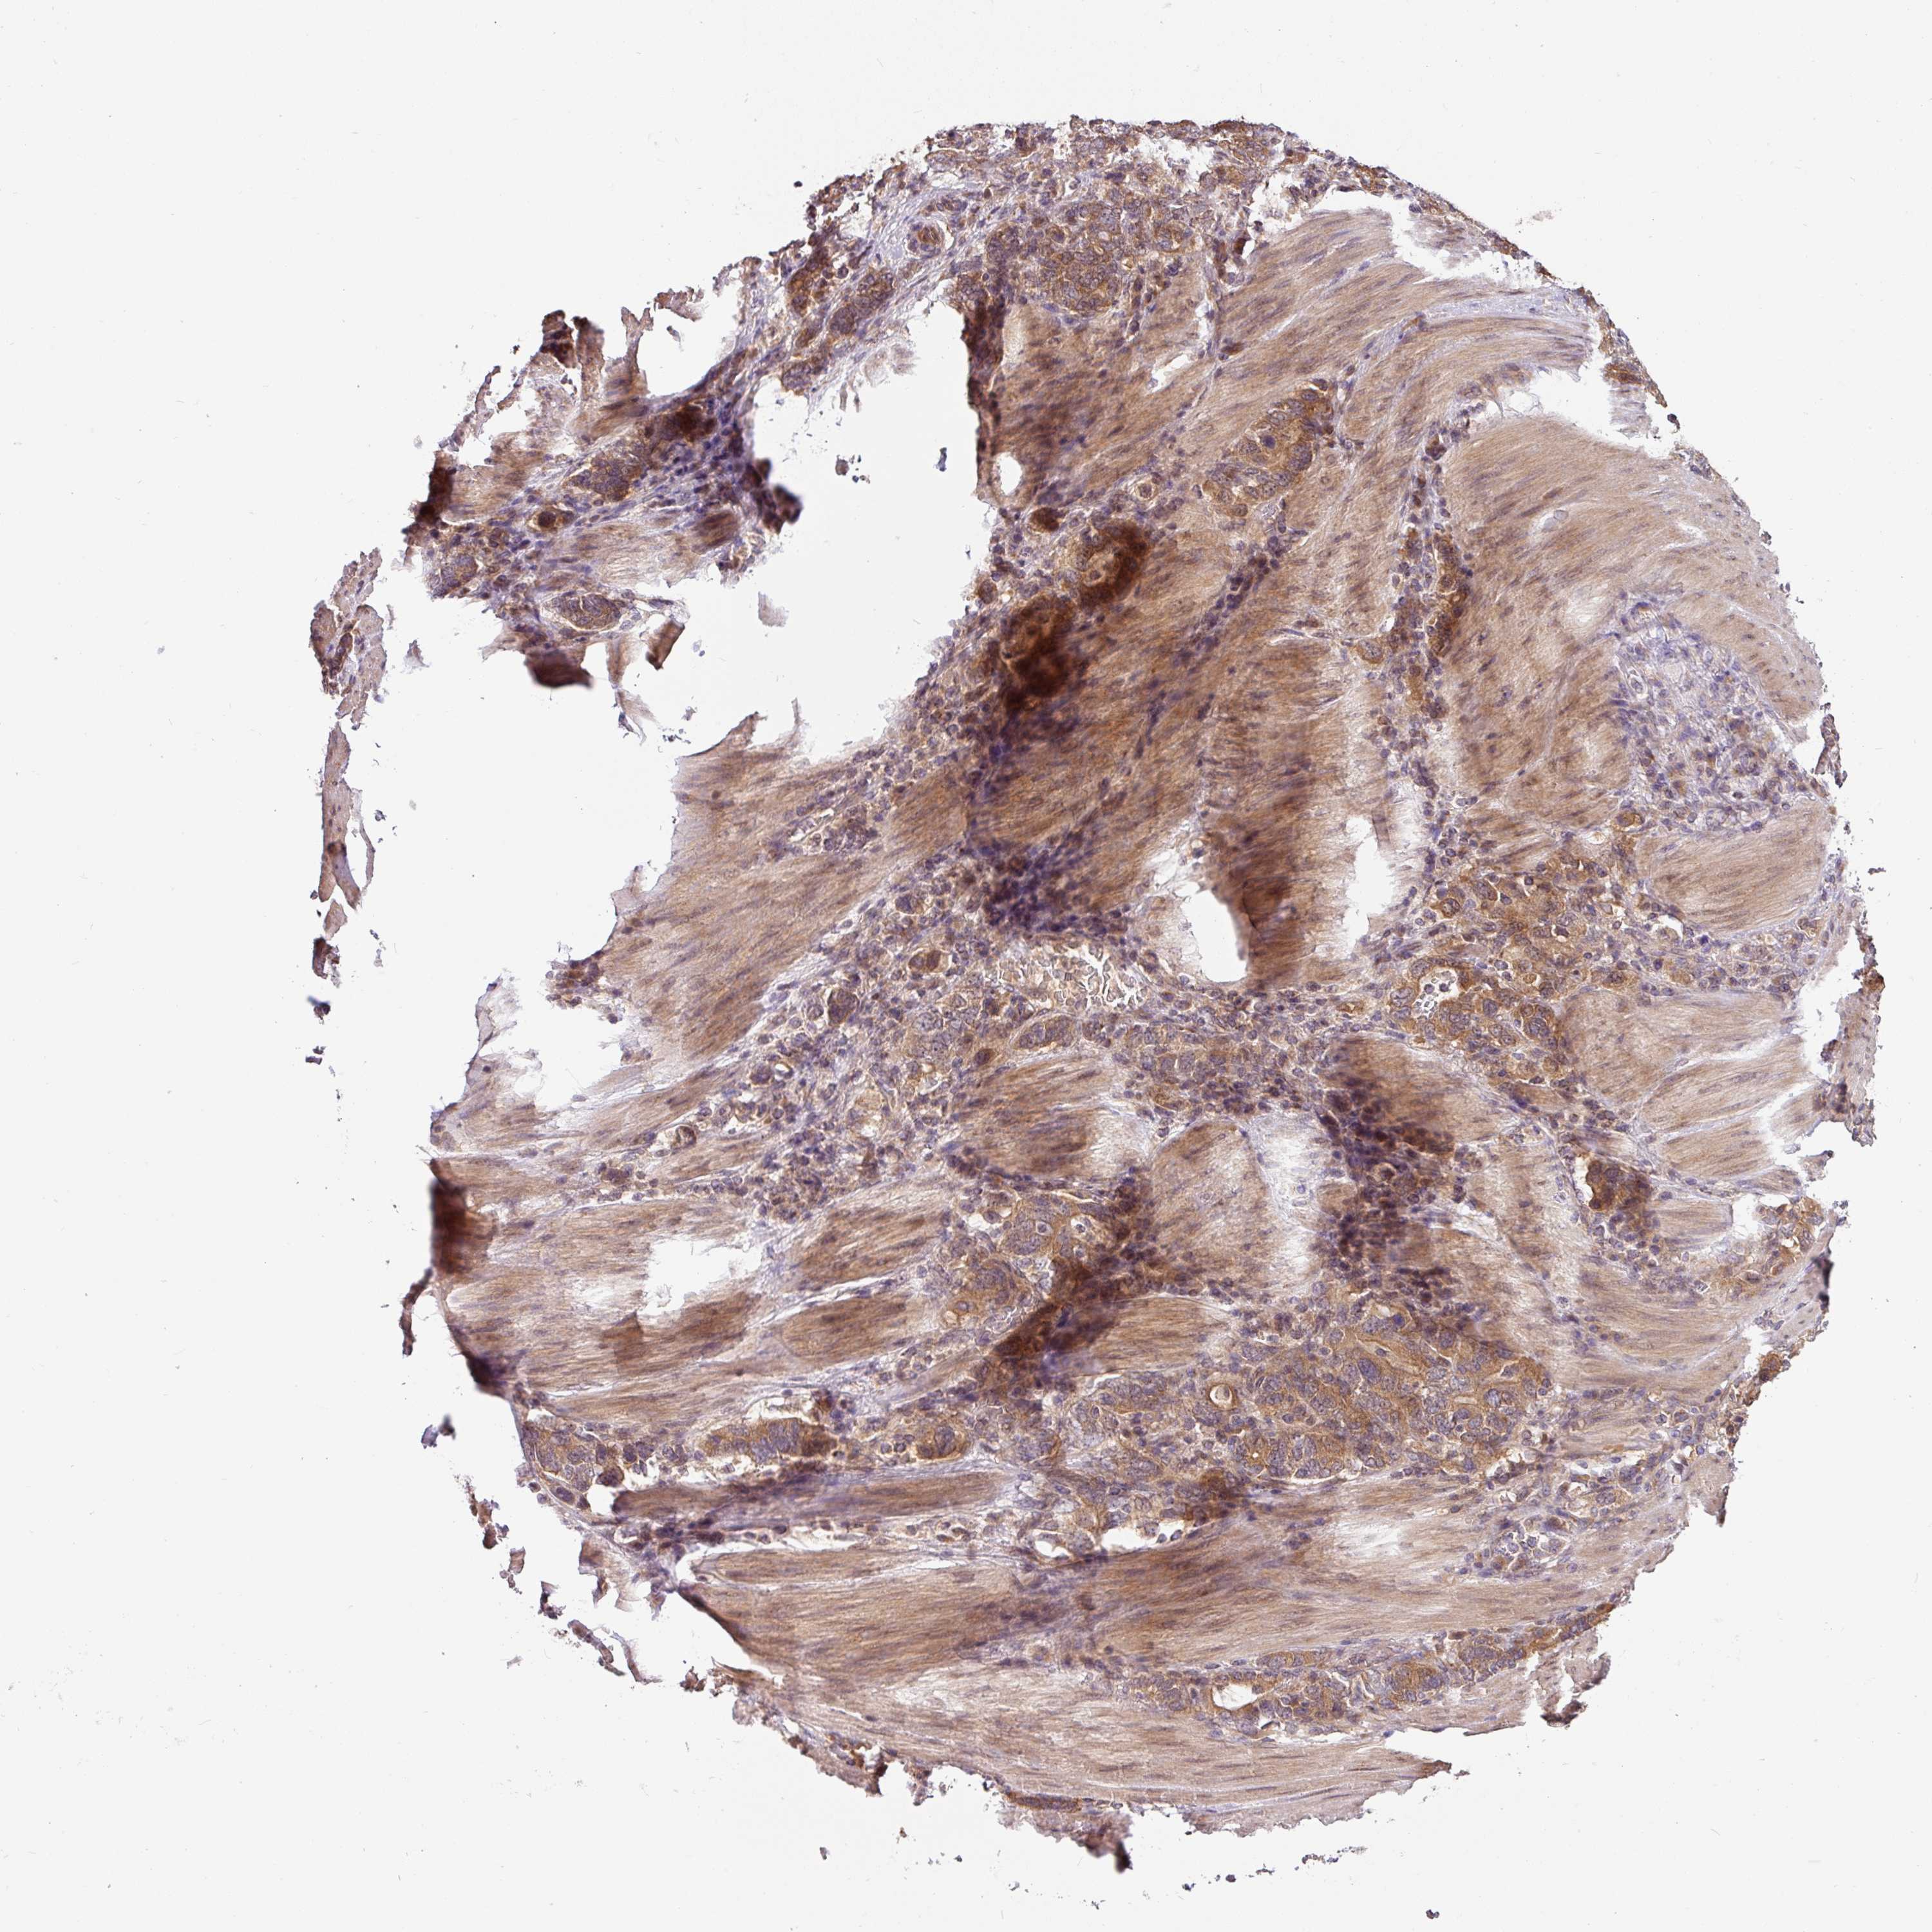

STOMACH CANCER - Protein expressioni

A mouse-over function shows sample information and annotation data. Click on an image to view it in a full screen mode. Samples can be filtered based on level of antibody staining by selecting one or several of the following categories: high, medium, low and not detected. The assay and annotation is described here.

Note that samples used for immunohistochemistry by the Human Protein Atlas do not correspond to samples in the TCGA dataset.

Antibody stainingi

Antibody staining in the annotated cell types in the current human tissue is reported as not detected, low, medium, or high, based on conventional immunohistochemistry profiling in selected tissues. This score is based on the combination of the staining intensity and fraction of stained cells.

Each image is clickable and will lead to virtual microscopy that enables deeper exploration of all samples and also displays staining intensity scores, fraction scores and subcellular localization as well as patient and tissue information for each sample.

Antibody HPA049911

Antibody CAB010161

Staining

High

Medium

Low

Not detected

Intensity

Strong

Moderate

Weak

Negative

Quantity

>75%

75%-25%

<25%

None

Location

Nuclear

Cytoplasmic/membranous

Cytoplasmic/membranous,nuclear

Adenocarcinoma, NOS